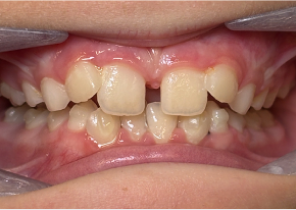

Báo cáo ca 2

7 tuổi 11 tháng, 24 bước nong của Nong hàm khẩu cái Invisalign®

Hàm được nong sau khi sử dụng nong hàm khẩu cái Invisalign®

Sau khi điều trị với Nong hàm khẩu cái Invisalign